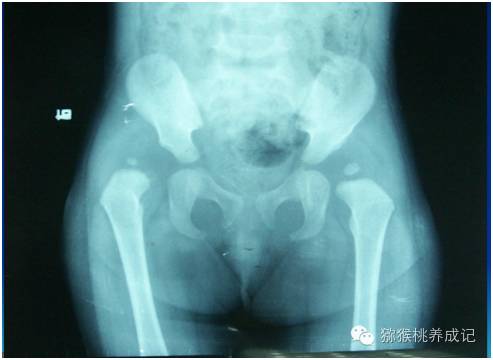

图为右侧髋关节脱位